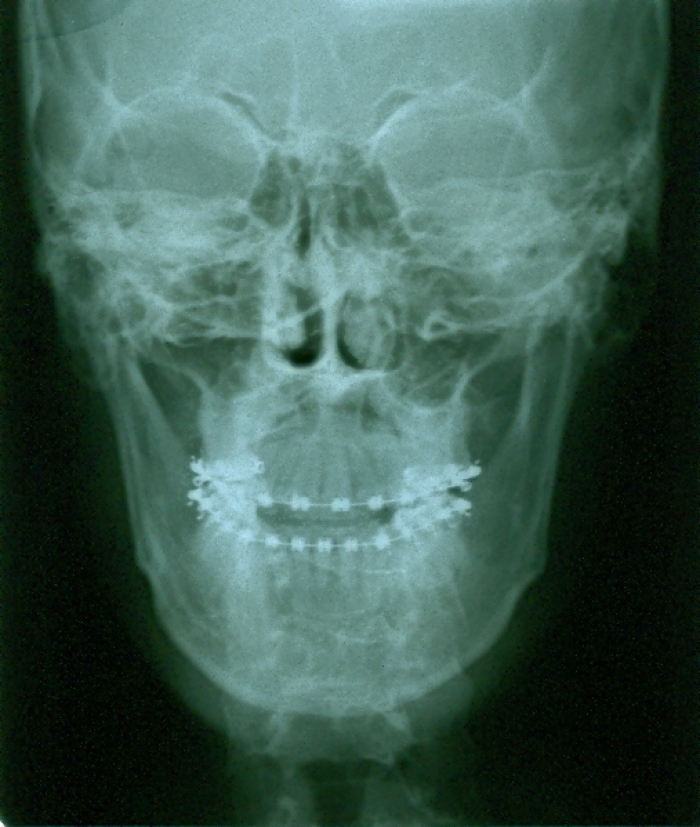

Telerradiografia frontal após a cirurgia